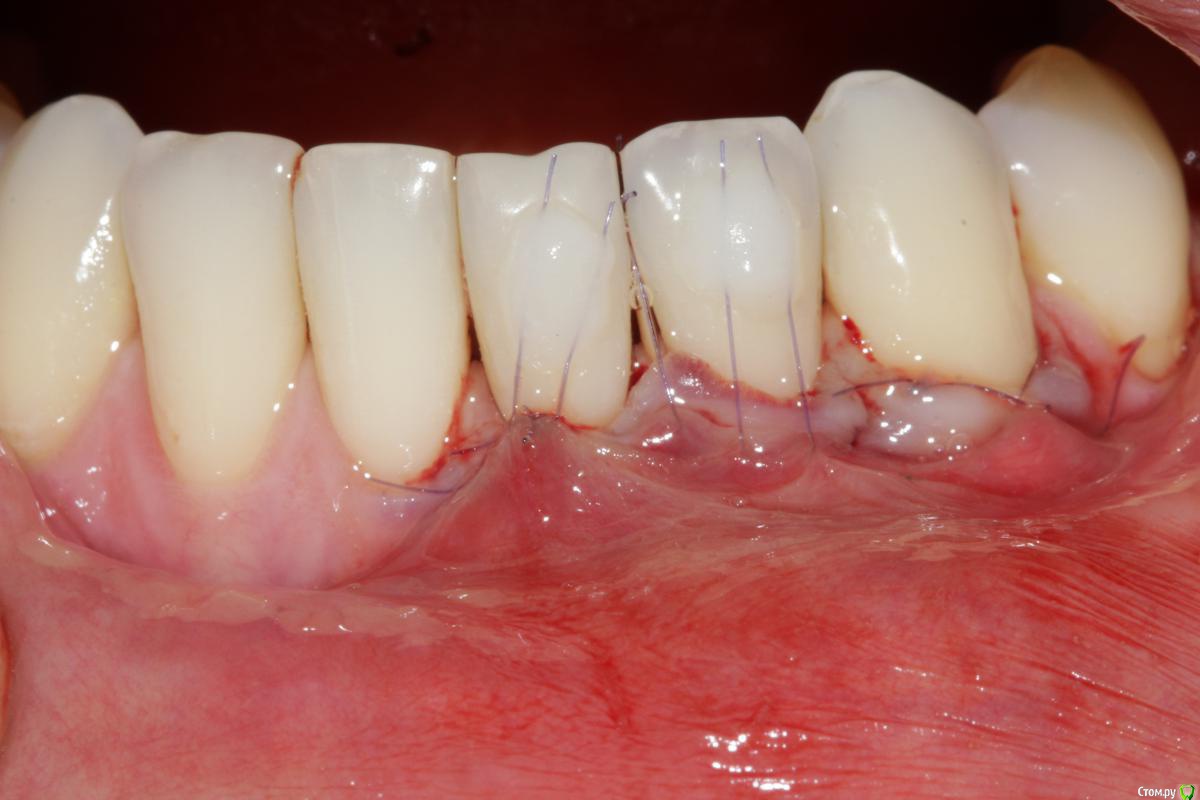

Dc.Petrov Опубликовано 18 сентября, 2015 Поделиться Опубликовано 18 сентября, 2015 Хочу узнать мнение коллег. Можно ли считать результат удовлетворительным? Рассчитывал на лучший итог. 15 Ссылка на комментарий

zzkz Опубликовано 19 сентября, 2015 Поделиться Опубликовано 19 сентября, 2015 через 3-6 мес можно точно сказать, на сегодня все нормуль. 31 еще можно подтянуть. Ссылка на комментарий

Dc.Petrov Опубликовано 21 сентября, 2015 Автор Поделиться Опубликовано 21 сентября, 2015 Почему четверку обошли стороной? Цель изначально была закрыть 31Сейчас уже жалею, что 34 не сделал Ссылка на комментарий

zzkz Опубликовано 22 сентября, 2015 Поделиться Опубликовано 22 сентября, 2015 До ЦЭС у 31 и 34 кажется что можно, по крайней мере по фото Ссылка на комментарий

Dc.Petrov Опубликовано 22 сентября, 2015 Автор Поделиться Опубликовано 22 сентября, 2015 с 34 понятно, с ним поработаю . Просто на одном том же месте (31) есть ли смысл повторять ? Ссылка на комментарий

zzkz Опубликовано 23 сентября, 2015 Поделиться Опубликовано 23 сентября, 2015 с 34 понятно, с ним поработаю . Просто на одном том же месте (31) есть ли смысл повторять ?если это возможно и нужно, конечно стоит. Можно даже и бесплатно. Я за повторную операцию беру только за расходник. Тут мне уже принципиально хочется добить рецессию)) Ссылка на комментарий